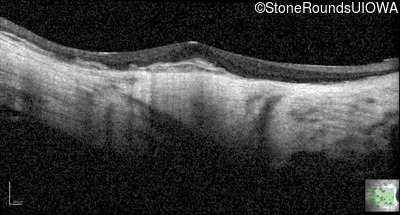

Optical Coherence Tomography - Left - 20/25 +2

Exemplar / OCT Stack

OCT Stack